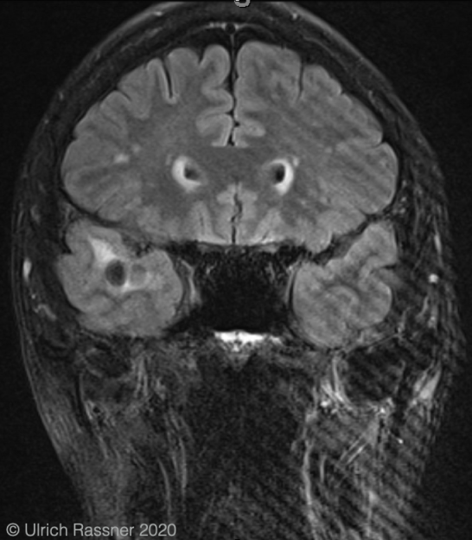

How can Gibbs artifact be minimized

Truncation errors (Gibbs artifact) can be minimized by increasing the number of phase-encode steps or by reducing the field of view.

What was the most likely step taken to eliminate the artifact seen in the first image?

Increasing the matrix size decreased truncation artifact (aka Gibbs, or ringing).

choosing a smaller FOV can also help eliminate this artifact